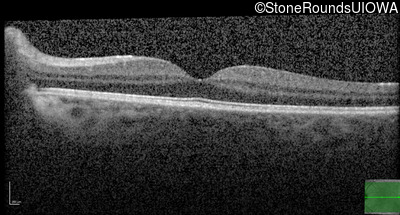

Optical Coherence Tomography - Left - 20/20 -1

Exemplar / OCT Stack